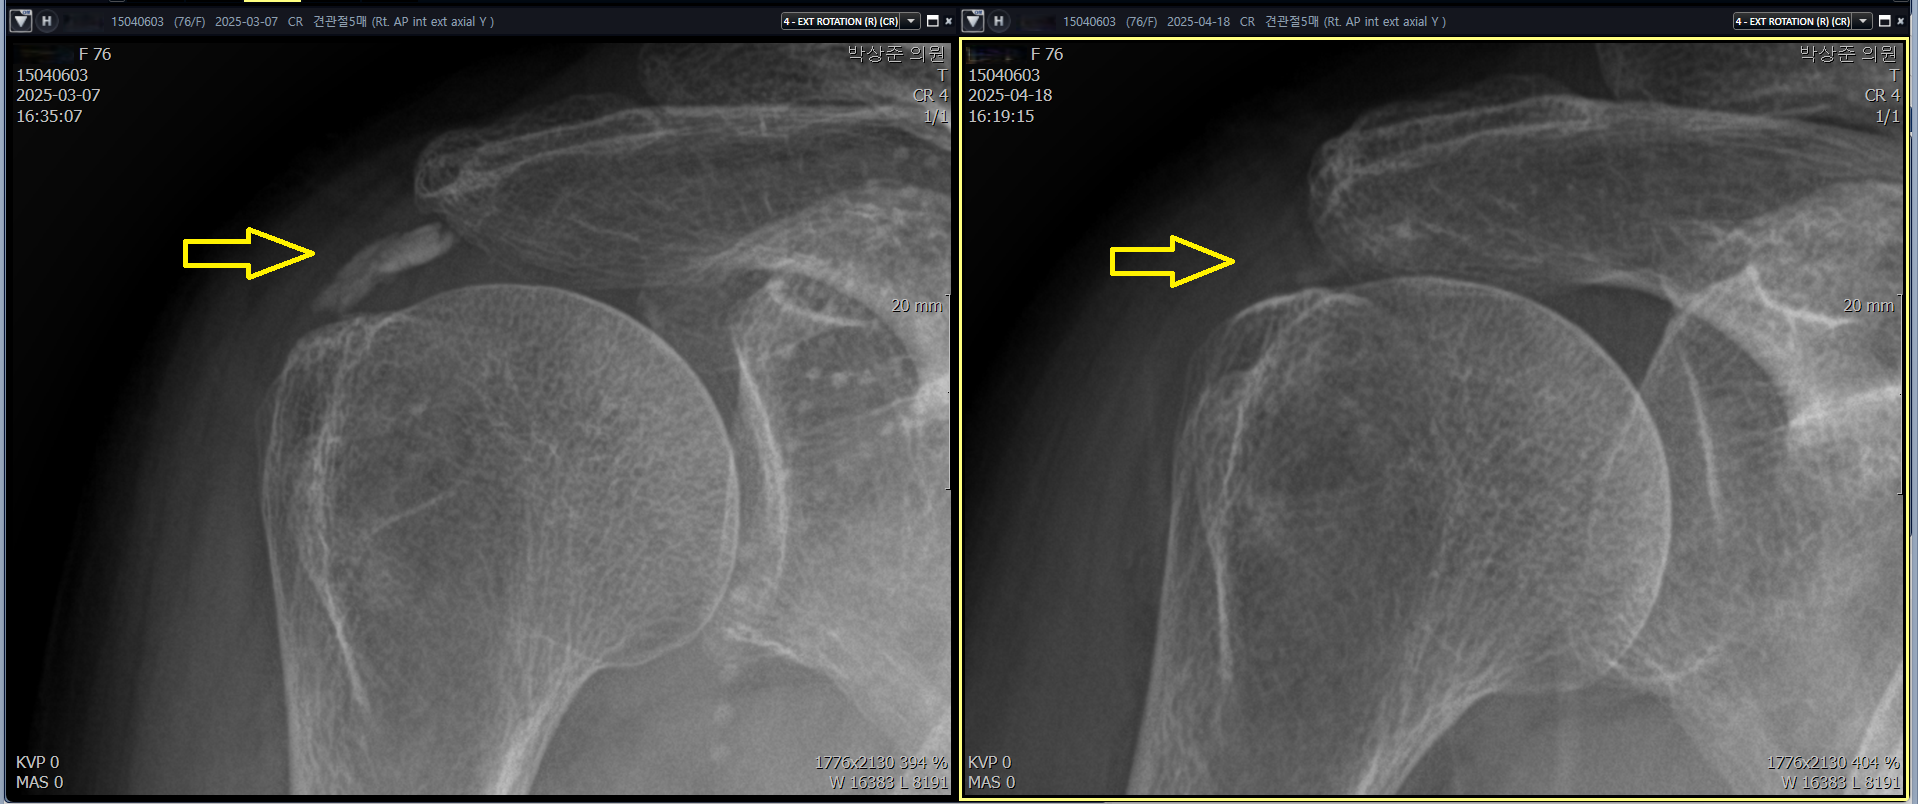

이 환자분은 이렇게 5회에 걸쳐서 초음파를 보면서 석회를 흡입하는 석회 흡입술 + 체외 충격파 치료를 시행했습니다. 그 결과는?

위에 비포 & 애프터 사진에서 보다시피 처음보이던 커다란 석회가 5회의 치료동안 약 90% 가량 사라진것을 확인할 수 있습니다.

나 : 석회가 예상한것보다 훨씬 더 많이 사라졌네요. 다행이에요

환자 : 정말 그러네요. 감사합니다.